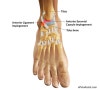

발목의 움직임시 발목 앞쪽 또는 뒤쪽의 구조물에 충돌이 일어나는 질병입니다.

과도한 배굴로 경골 전방 가장자리와 거골 배측이 충돌하거나 과도한 저굴로 인대나 관절낭에 과도한 견인력이 작용하거나 염좌를 반복한 결과로 생각됩니다.

크게 Anterior impingement, Posterior impingement로 나뉠 수 있습니다.

Cf) Anterolateral impingement

Three theories : Chronic injury to ATFL, Scar tissue, Hypertrophied anomalous ligament

Usually occurs after relatively minor, inversion/forced, plantar flexion, trauma; usually not unstable Often remains a clinical diagnosis.

Cf) Anteromedial impingement

Rare complication of inversion injury with perhaps a rotational component; leads to AM capsular injury, cartilage injury, osteophytes.